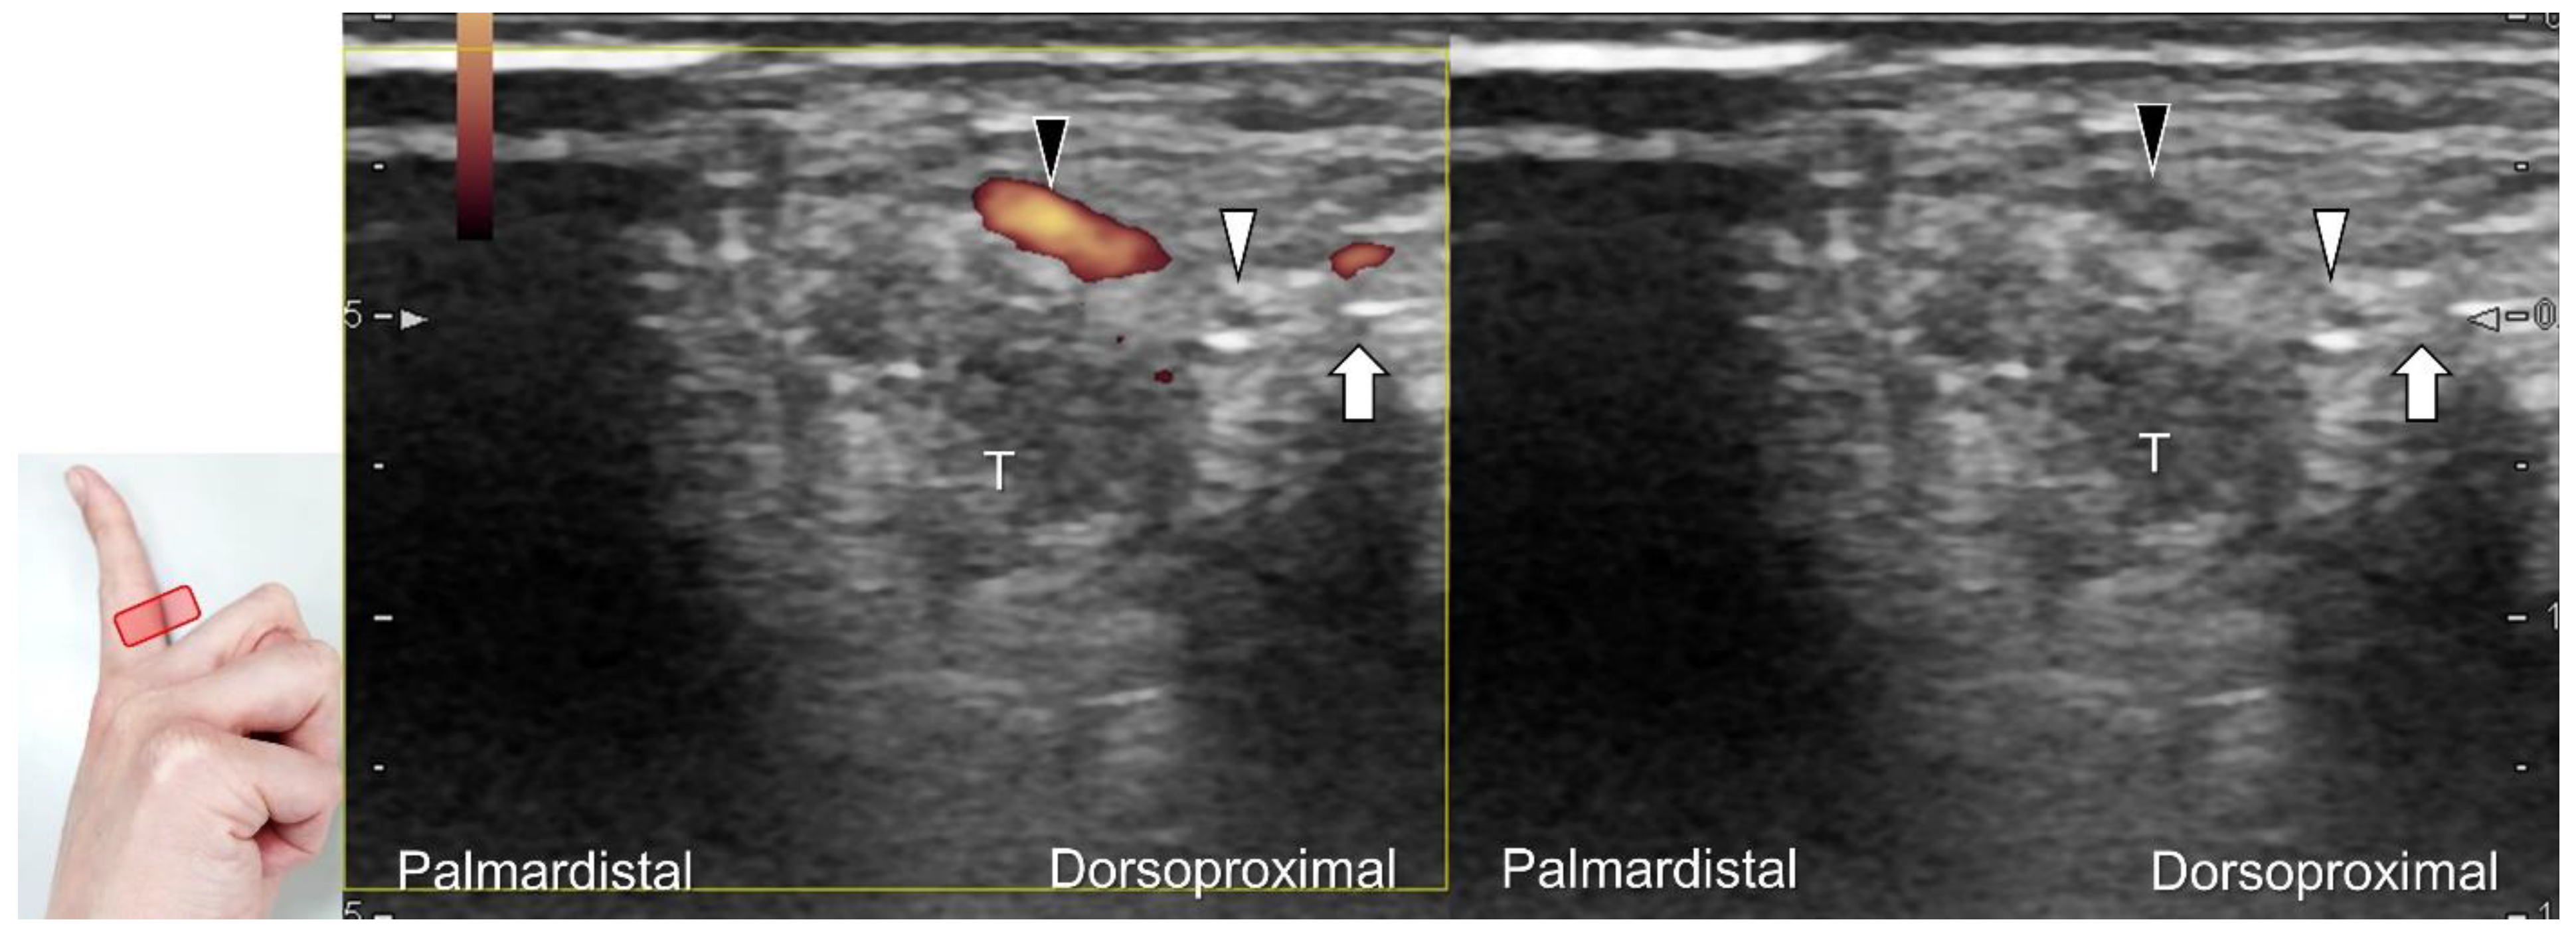

US imaging may reveal a neuroma in cases where patients report chronic allodynia and/or tingling sensation in the affected digit (Figure 36). To perform hydrodissection, the in-plane approach can be utilized in the nerve’s short axis after identifying the extensor digitorum tendons and the dorsal metacarpal arteries (Figure 37).

Figure 37. Ultrasound-guided injection to the dorsal proper digital nerve in its short axis with the dual imaging mode (Doppler vs. B mode). White arrowhead: dorsal proper digital nerve; black arrowhead: dorsal proper digital artery; arrow: needle. T: flexor tendons.